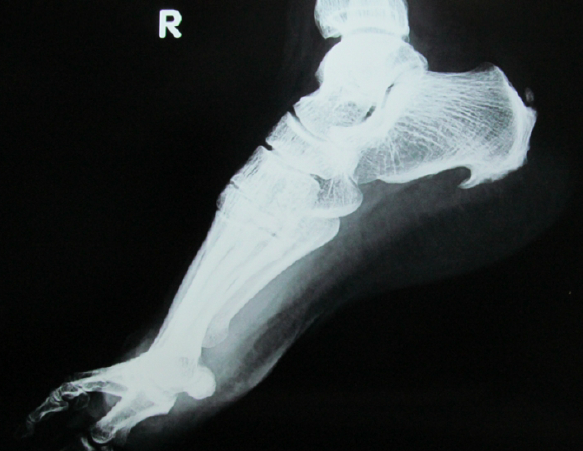

Producido por una acumulación de calcio y el crecimiento de un hueso del talón en forma triangular, el espolón calcáneo provoca un dolor agudo en los pacientes. Sus primeros síntomas se originan en la parte interna del talón eincrementa en situaciones donde el pie tiene un funcionamiento más intenso y, por lo tanto, una sobrecarga originada, en muchas ocasiones, por el aumento de la tensión en la fascia plantar.